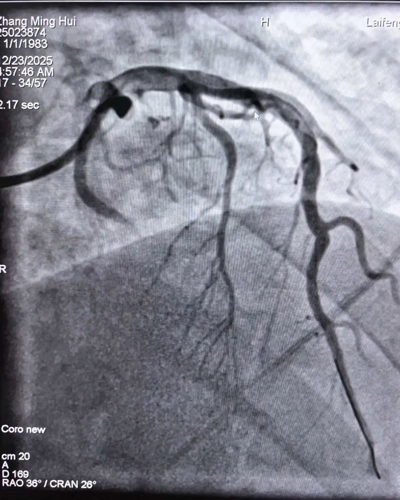

手术前血管情况 手术后血管情况